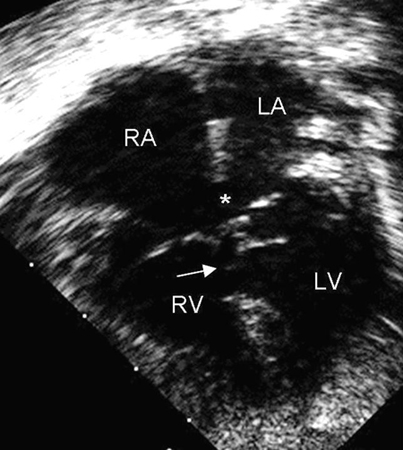

Imagen de ecocardiografía de 4 cámaras apical de una comunicación auriculoventricular (CAV) completa. Observe la comunicación interauricular (CIA) de tipo ostium primum (*) y la comunicación interventricular (CIV) de entrada contigua (flecha). (AD) aurícula derecha; (AI) aurícula izquierda; (VD) ventrículo derecho; (VI) ventrículo izquierdo